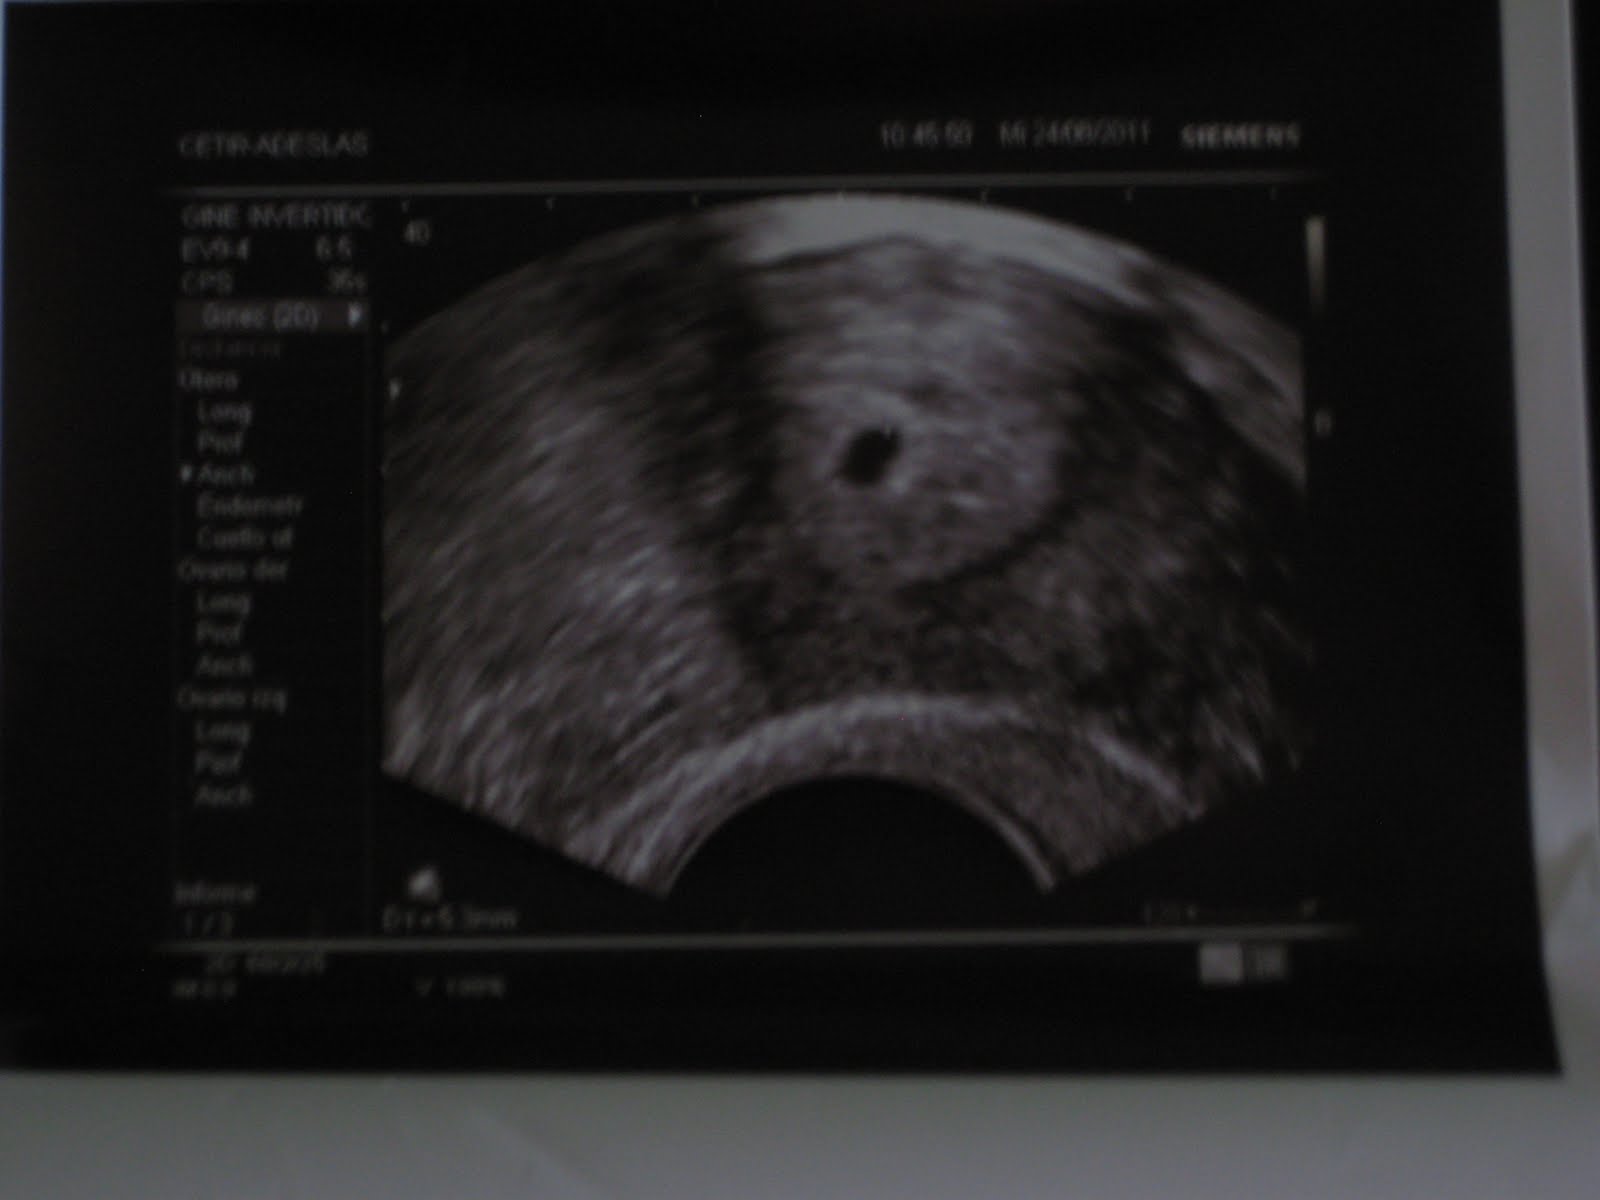

Primera Eco Tras Beta Positiva, De la Beta positiva a la primera ecografía. Unas semanas difíciles de gestionar., 5.91 MB, 04:18, 4,799, C'Est La Vie, Noemí!, 2020-03-12T13:32:38.000000Z, 3, Valores Beta Positiva Fiv Discount Buy, Save 42% | jlcatj.gob.mx, www.jlcatj.gob.mx, 1200 x 1600, jpeg, WebLos primeros días después de una beta positiva suelen ser de felicidad absoluta, pensamos que nuestro sueño se ha cumplido y que, por fin, después de. WebEscorpio, es imposible intuir a través de la beta si se trata de un parto múltiple o no. La mejor manera de saber si se trata de un embarazo múltiple es a través. Web¿Cuándo realizar la primera ecografía de embarazo tras los tratamientos de FIV? Se debe realizar entre la 5ª y la 7ª semana de gestación, es decir entre 3 y 5 semanas tras la., 20, primera-eco-tras-beta-positiva, Novedades y Muebles WebLos primeros días después de una beta positiva suelen ser de felicidad absoluta, pensamos que nuestro sueño se ha cumplido y que, por fin, después de. WebEscorpio, es imposible intuir a través de la beta si se trata de un parto múltiple o no. La mejor manera de saber si se trata de un embarazo múltiple es a través. Web¿Cuándo realizar la primera ecografía de embarazo tras los tratamientos de FIV? Se debe realizar entre la 5ª y la 7ª semana de gestación, es decir entre 3 y 5 semanas tras la.

Web1era eco sin embrión y prueba positiva alguien igual? - Página 3: hoy he tenido mi primera eco en principio estoy de 6.6 pero no habiA embrión ni saco...me he. Web¡Hola de nuevo, preciosas!La #betaespera ha acabado y ya tenemos el resultado... #BetaPositiva :) :) :)¡Os lo cuento todo en el vídeo WebLa beta-hCG se empieza a detectar a partir de la tercera o cuarta semana de embarazo y se incrementa durante todo el primer trimestre. A partir de la semana 12,. Web5º- Semana 7: Todas te harán una eco para confirmar el latido del corazón y la mayoría te darán el alta. (El momento latido no lo vas a olvidar nunca) Como ves sólo hay consenso. WebHola a todas. El día 2 de marzo me hice la transfer del único embri que conseguí en mi primera ICSI. El día 16 me hicieron la beta y dio positivo, así que me. WebLa primera ecografía tras conocer el embarazo es un momento inolvidable y crucial, sobre todo si se produce tras un Tratamiento de Fecundación In Vitro. Aunque los. WebAunque el análisis de la beta hCG en sangre haya dado positivo, normalmente hasta al menos la semana 6 de embarazo no se empieza a ver nada en la. WebHola lunita, claro que lo importante es que la beta esté bien. Y además despues de 7 intentos es mi primer positivo. Solo quiero hacer como un estudio de betas.